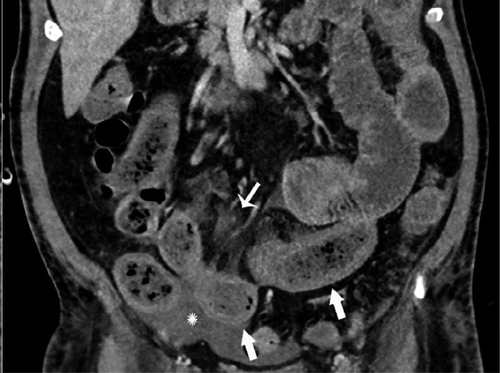

В частности, как пояснил специалист, у некоторых пациентов с COVID-19 внезапно развивался пневматоз - патологическое состояние системы пищеварения, при котором газы проникают в толщу стенки кишечника и образуют там воздушные кисты. Кроме того, у нескольких людей было выявлено необычное желтое обесцвечивание кишечника, еще у трех больных - инфаркт кишечника.

© Radiology